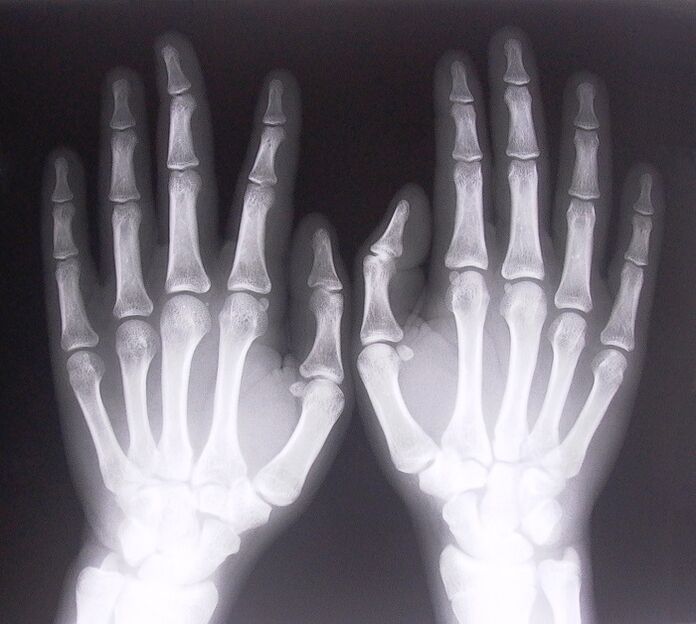

- Steneuze ligamentitis. Om de oorzaak van de ziekte te identificeren, is het noodzakelijk om een röntgenfoto te ondergaan. Symptomen zijn typisch: pijnlijke beweging van de hand, lusvorming van de gebalde handpalm. Ook zijn er tijdens het uitschuiven meestal klikken hoorbaar.

- Maak röntgenfoto's.